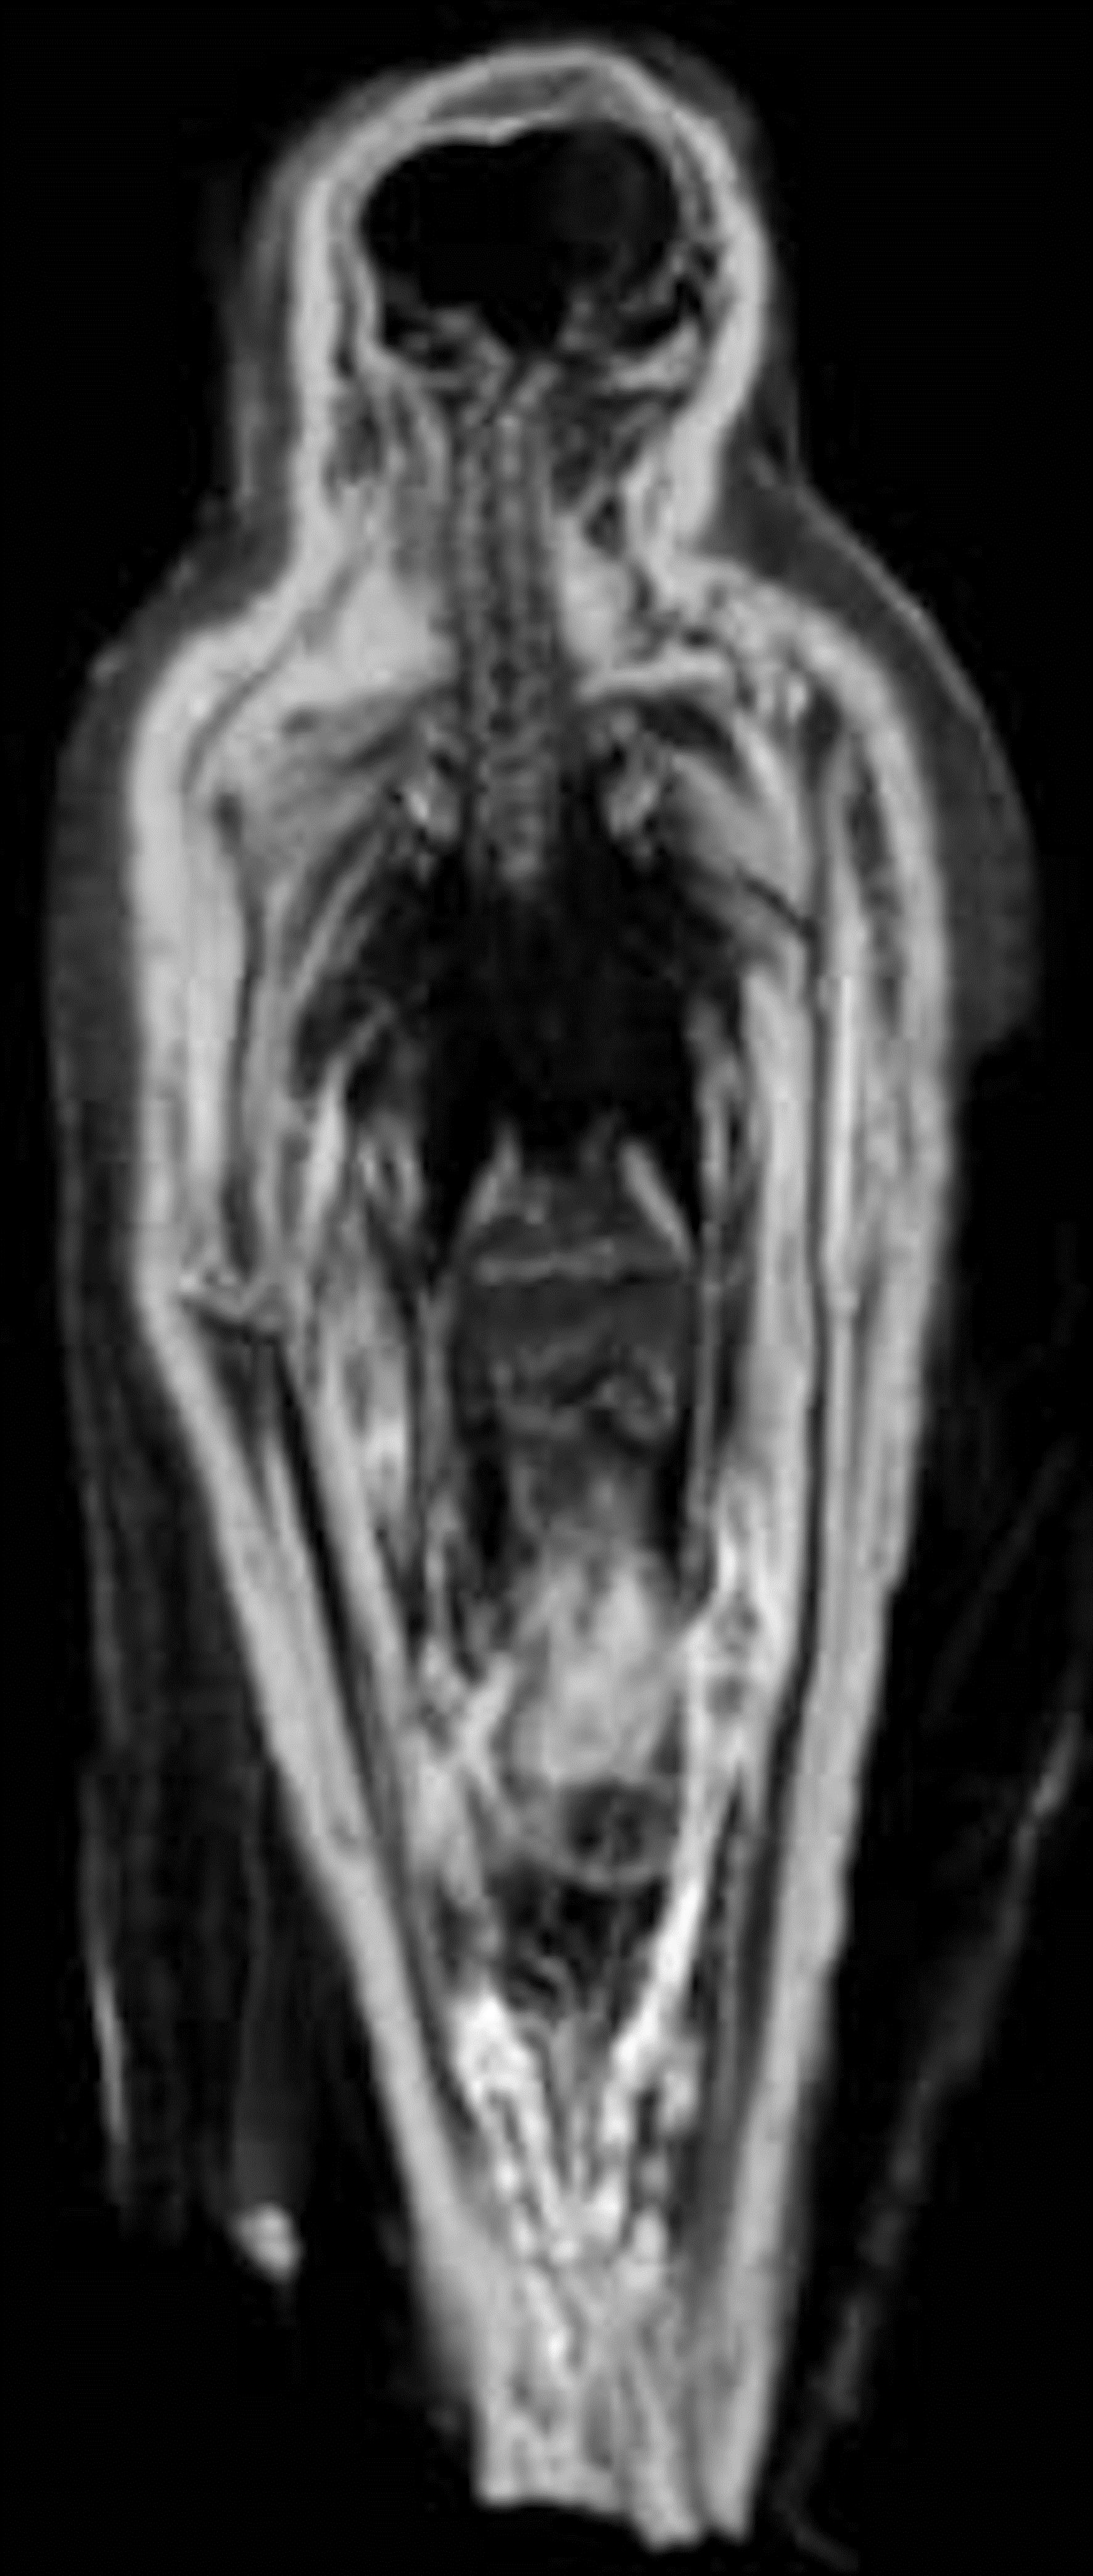

Radiographic observations

A lack of evisceration was observed (McKnight and Atherton in press) with several complete and articulated bird mummies identified as small birds of prey, mostly Falco tinnunculus (Kestrel) and Accipiter nisus (Sparrowhawk). The internal organs were thought to have become dehydrated and, as a result, had decreased in size within the abdominal cavity, and appeared as radiopaque shadows on radiographic images (See Figure 2).